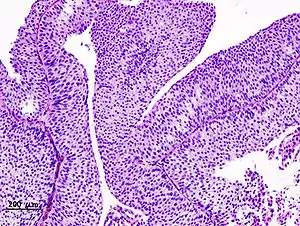

Non-papillary carcinoma includes carcinoma in situ (CIS), microinvasive carcinoma and frankly invasive carcinoma.[68] Carcinoma in situ (CIS) invariably consists of cytologically high-grade tumour cells.[69]

Transitional cell carcinoma can undergo differentiation (25%) into its variants.[68][70][71] When seen under a microscope, papillary transitional cell carcinoma can present in its typical form or as one of its variations (squamous, glandular differentiation or micropapillary variant). Different variations of non-papillary transitional cell carcinoma are listed below.